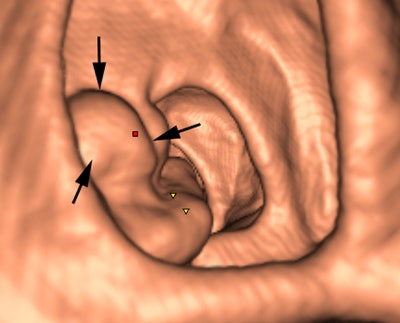

CAD for colonography has shown particular promise, and most radiologists will come across it in their workflow and will need to understand sensitivity and specificity issues, as well as when CAD should be deployed in this area. The technique's major diagnostic benefits are in small 6- to 9-mm polyps, which often are difficult for the radiologist to spot.

"CAD acts like a spell-check for small polyps," said Dr. Stuart Taylor, professor of medical imaging and consultant gastrointestinal radiologist at University College London, in an interview ahead of the congress. "There are also instances when tumors and large polyps are missed by the radiologist before CAD draws attention to them."

False negatives can present a challenge too. Typically the computer program looks for the rounded bowler-hat contours of a polyp that stand proud of the bowel wall. It may miss the flatter polyps and even large mass-like lesions that don't have typical rounded contours.

Evidence suggests that second-read CAD is more effective in increasing sensitivity but adds to reporting time, he explained. "Conversely, while concurrent reading may take less time, radiologists can be tempted to only look at CAD marks, which may distract them from scrutinizing nonprompted parts of the colon where there may be lesions."

A large multicentre Italian screening study has pointed to greater time efficiency of using double-reading first-reader CAD (DR FR CAD). CAD initially reads the image, and this first interpretation is around 90% sensitive. Then the radiologist looks at the image with a primary 2D read. In experienced hands, this double-reading paradigm works well and leads to fast and accurate reporting, according to the project's emerging data (Radiology, September 2013, Vol. 268:3).